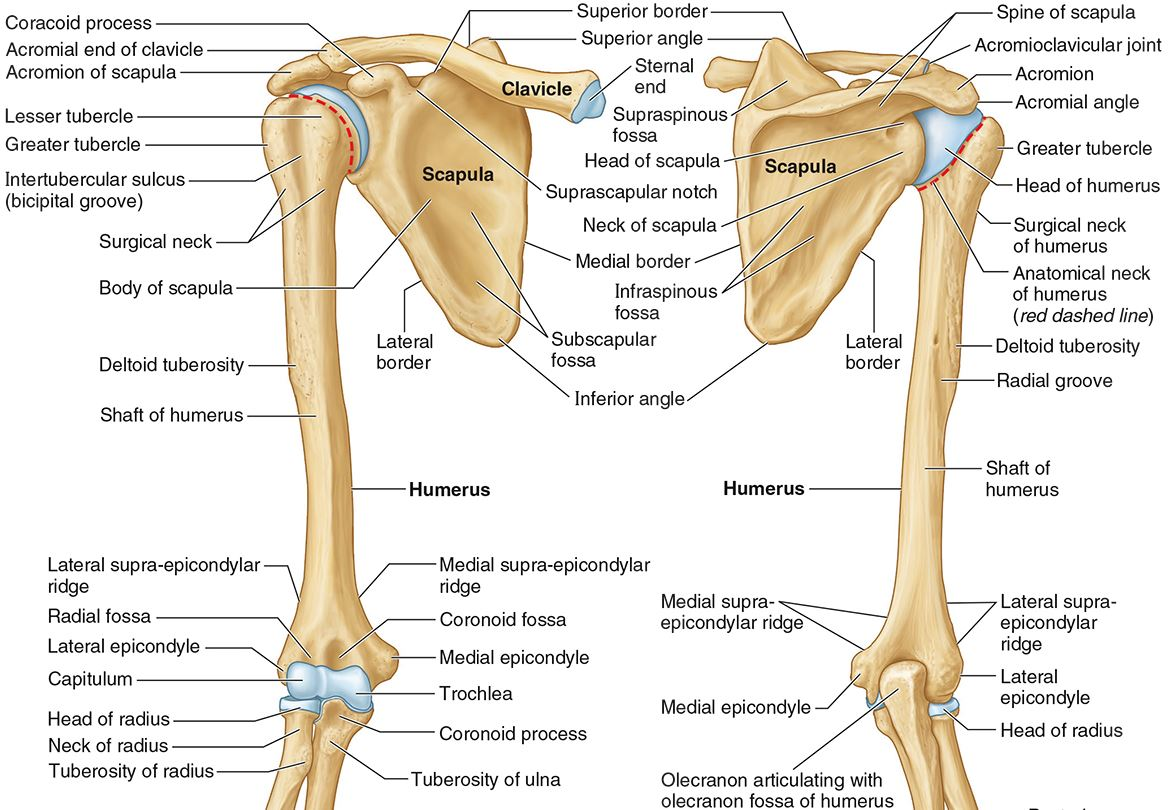

What part of the humerus is this?

The head of the humerus articulates with the scapula at the glenohumeral joint.

What part of the humerus is this?

The anatomic neck is an indentation distal to the head and provides an attachment for the fibrous joint capsule of the glenohumeral joint.

What part of the humerus is this?

The greater tubercle lies lateral and distal to the anatomic neck.

What part of the humerus is this?

The lesser tubercle lies on the anterior/medial side of the humerus, just distal the anatomic neck.

What part of the humerus is this?

The intertubercular (bicipital) groove lies between the greater and lesser tubercles.

What part of the humerus is this?

The surgical neck is a narrow area distal to the tubercles. It is a common site for proximal humerus fractures.

What part of the humerus is this?

The humeral shaft features the deltoid tuberosity laterally for the distal insertion of the deltoid muscle.

What part of the humerus is this?

The radial groove is an oblique depression that contains the radial nerve and deep brachial artery.

Which parts of the humerus is this?

The medial and lateral epicondyles are distal prominences to which many forearm tendons attach, near the elbow joint.

Which parts of the humerus is this?

The medial and lateral supracondylar ridges extend superiorly from the medial and lateral epicondyles.

Which parts of the humerus is this?

The trochlea and the capitulum (the condyles) are the most distal surfaces of the humerus, where it articulates with the forearm bones at the elbow joint

What part of the humerus is this?

The olecranon fossa is a posterior depression above the trochlea that receives that olecranon process of the ulna

What part of the humerus is this?

The coronoid fossa is an anterior depression above the trochlea that receives that coronoid process of the ulna.